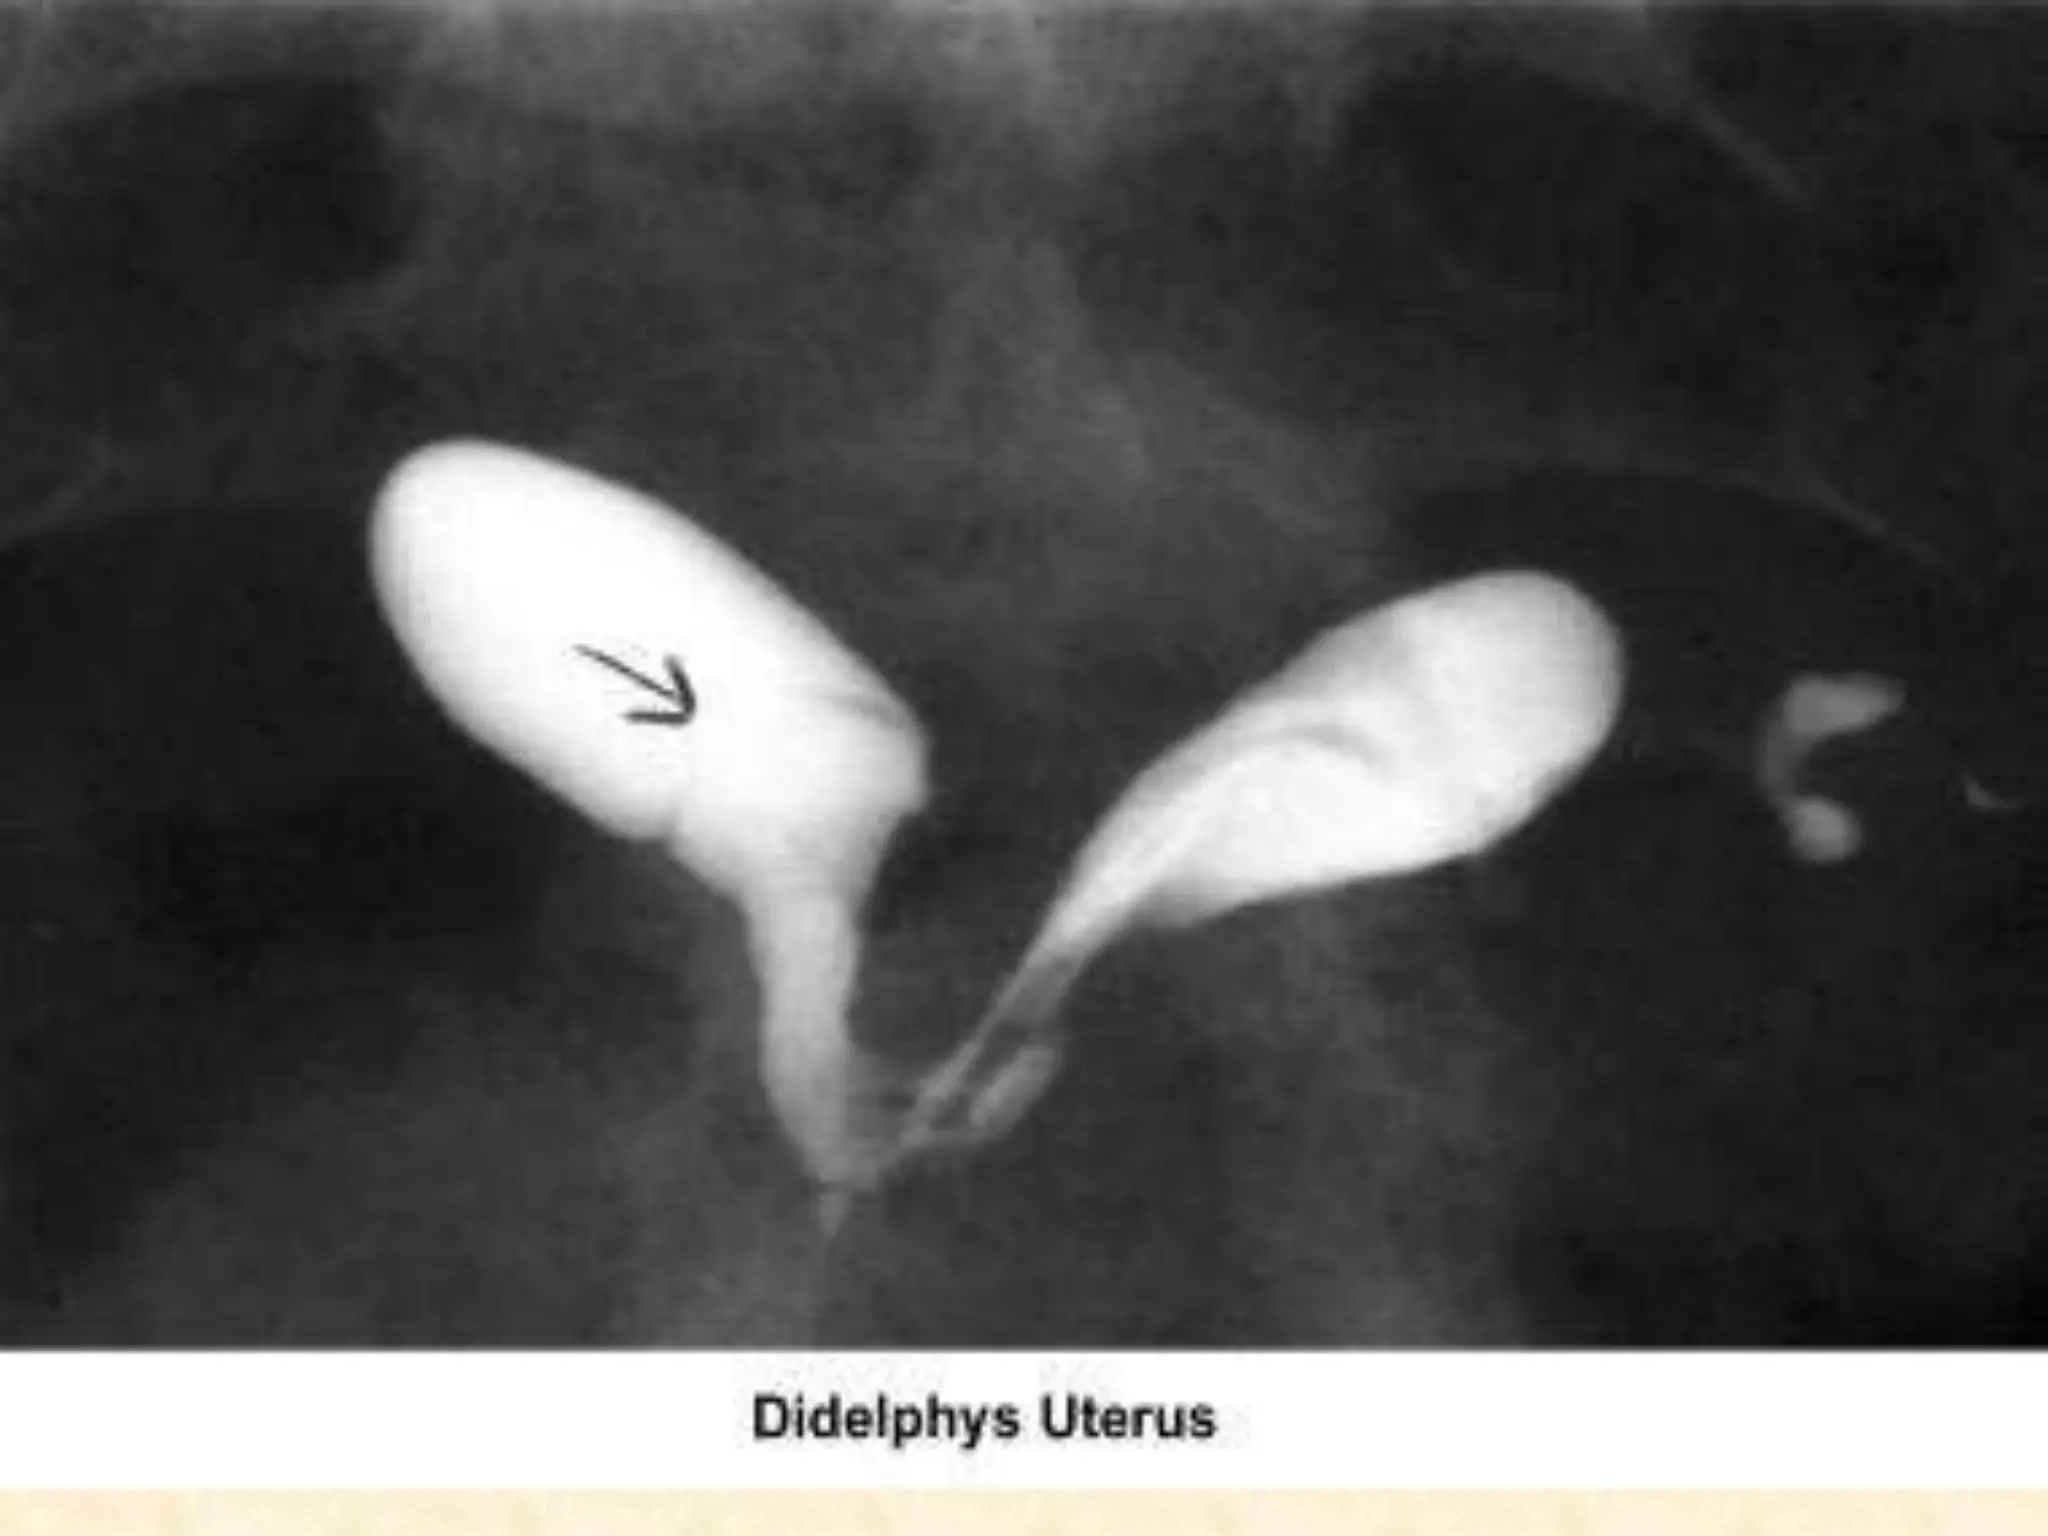

HSG show Congenital anomalies :

I. Hysterosalpingogram :

 The HSG is the most frequently used diagnostic tool

to evaluate the endometrial cavity.

 provides accurate information about the :

o endocervical canal

o diameter and configuration of the internal os

o endometrial cavity

o uterine/tubal junction (cornual ostium)

o diameter, location, and direction of the fallopian tubes

o status of the fimbriae

o spill into the endometrial cavity.

 The HSG should be performed during the early

follicular phase. At this time, the endometrium is thin

and the HSG provides better delineation of minor

defects.

 HSG is fluoroscopic study performed by instilling

radioopaque dye into uterine cavity via a catheter .

 The use of water-based contrast media is preferable

to oil-based media to avoid the risks of oil embolism

and granuloma formation.

 Peritonitis is a risk of procedure observed in upto 1-

3% of patients .

 Abnormal finding include :

o Congenital malformation of the uterus.

o Submucous leiomyomas

o Intrauterine synechiae (asherman syndrome)

o Intrauterine polyps

o Proximal or distal tubal occlusion .

o Salpingitis isthmica nodusa